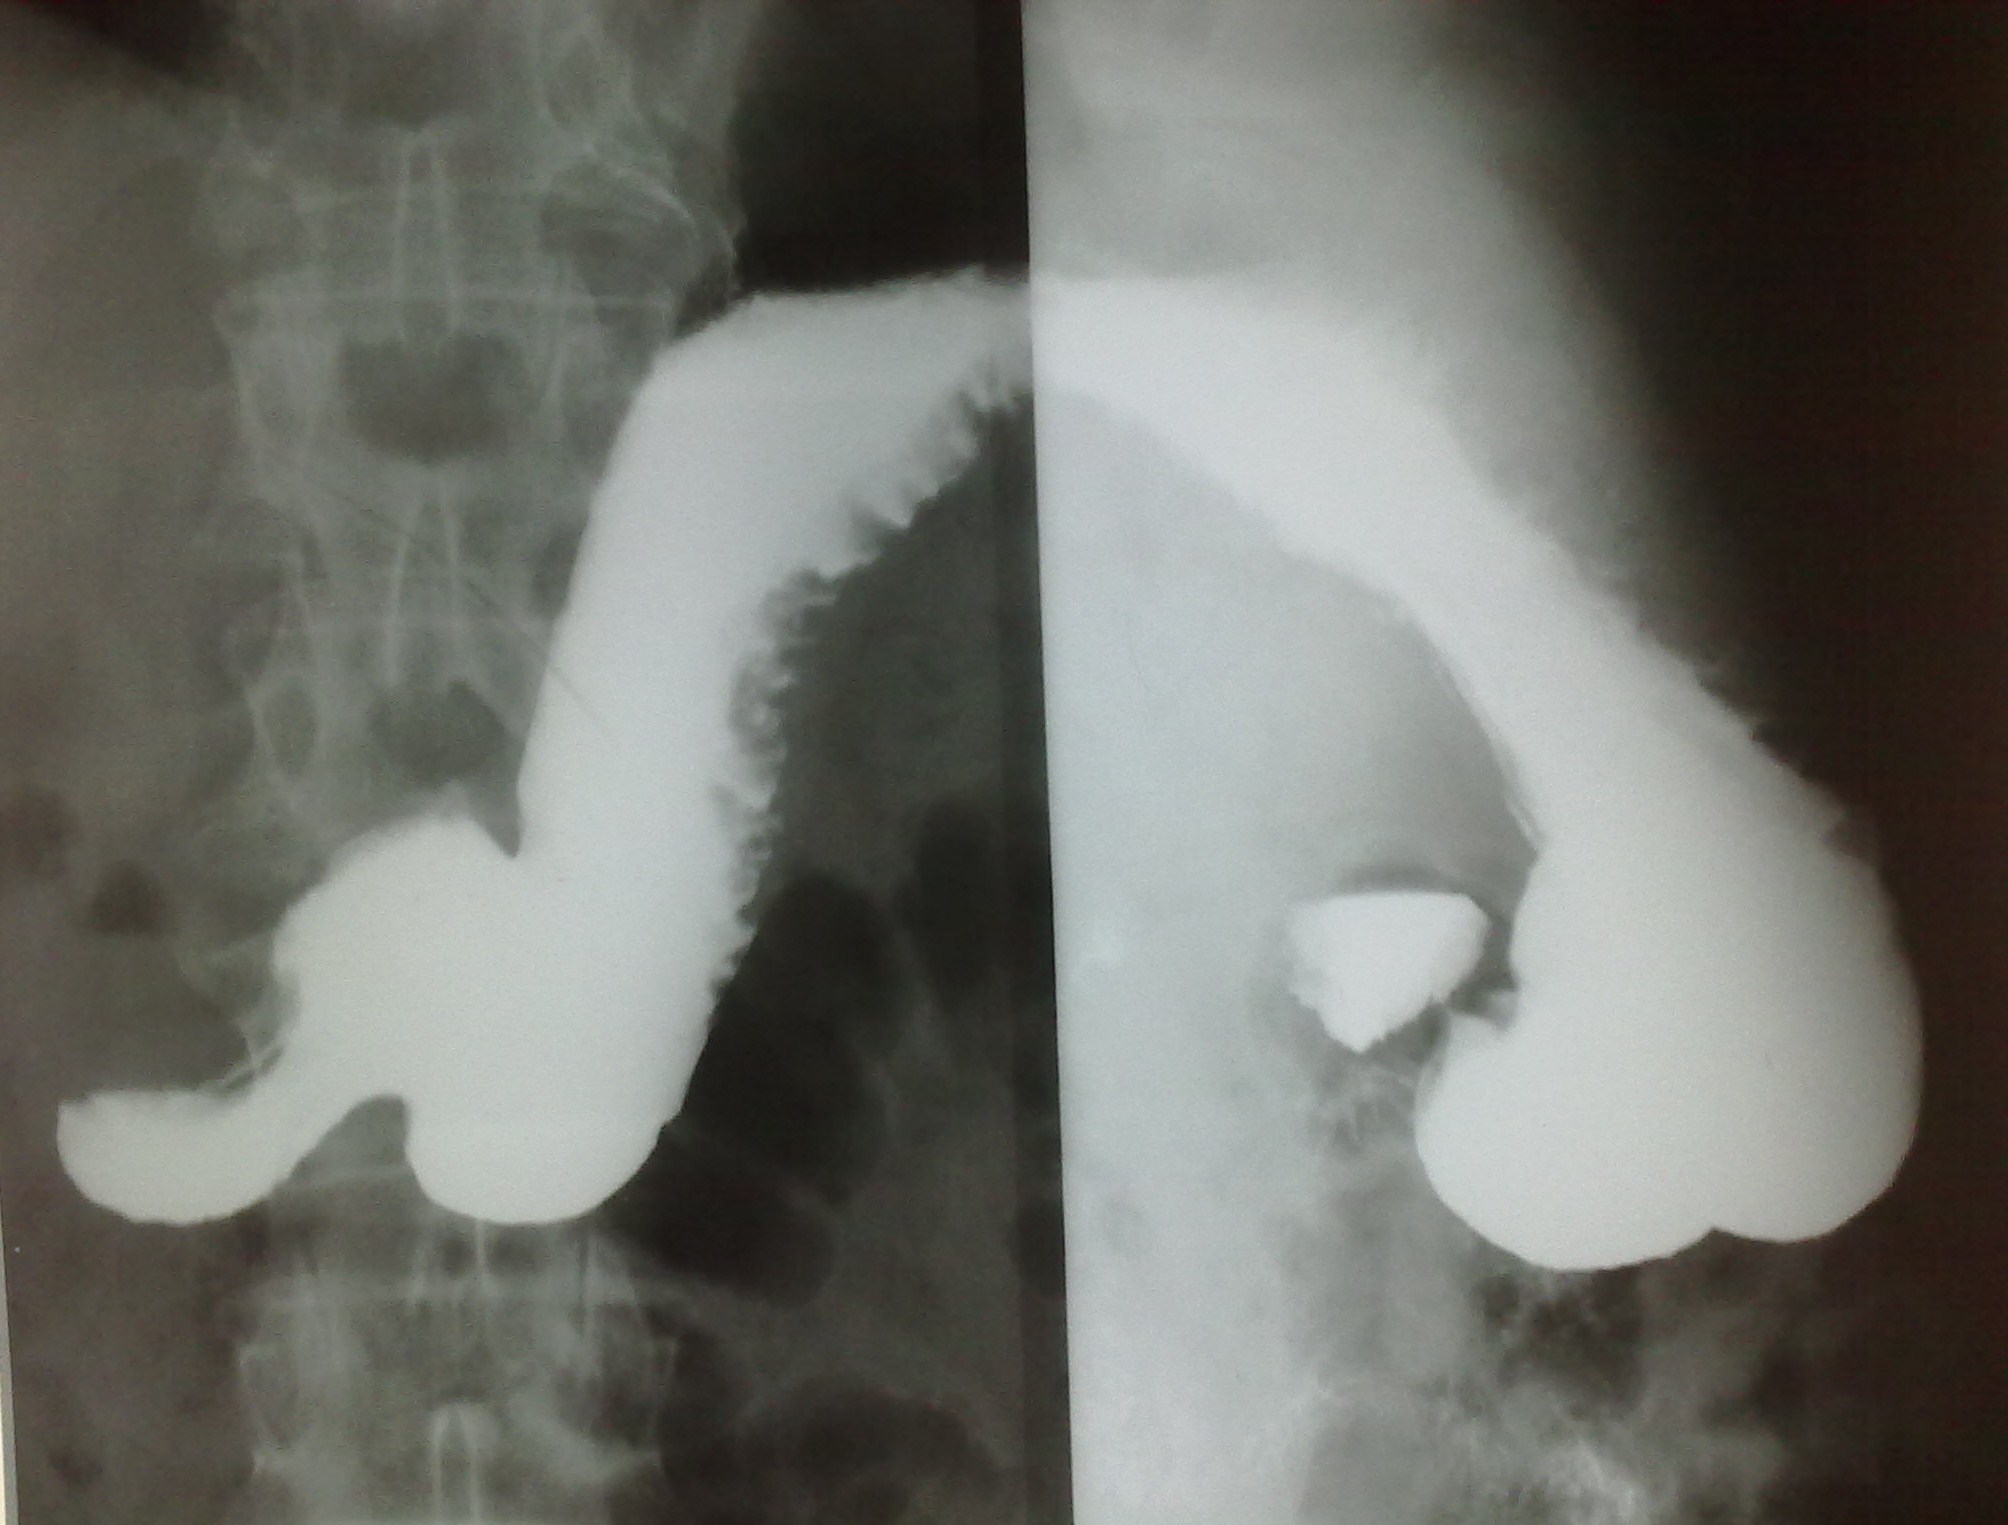

На большой кривизне физиологическая зазубренность. Это нормальная картина. Насчет грыжи - может это не грыжа, а просто рефлюкс контраста? Автору за экраном виднее было, как грыжа себя вела?

+1.Скорее всего, это не грыжа (пищеводного отверстия диафрагмы), а так получается пищеводая ампула( кратковременная картина "кольца сатурна "-инвагинация пищевода в пищевода - вариант нормы); т.к. дистальнее этого расширения видны тонкие пищеводные складки ( при грыже, были бы видны широкие желудочные складки слизистой).

ГПОД или нет - на откуп смотрящему. Рельеф слизистой гастритический: складки по большой кривизне разновеликие, неравномерные, избыточные, в антруме имеют косой ход (хотя полноценного раздувания двойного нет, судить адекватно не получится).

Ну, как Вы понимаете, по снимкам рельефа сторонний наблюдательно может напридумывать что угодно. Поэтому, если позволите, то по методике. Представлено 5 снимков. Каких нет? Нет прямого в вертикальном положении с контрастированной 12-перстной кишкой; нет лежа на животе с приподнятым левым боком и контрастированным пищеводом (именно в этой проекции определяется ГПОД), нет лежа на спине с приподнятым правым боком (для оценки пилоробульбарной зоны), нет левого бокового снимка стоя после снимков лежа (для оценки купола и задней стенки желудка). Снимок №4 (кроме того, что не контрастирована 12-перстная кишка) провоцирует больше вопросов, чем дает ответов: можно придумать дефект наполнения по малой кривизне в антральном отделе и пальцевое вдавление по большой по типу "перста указующего" (стрелки) И еще - гиперпластический гастрит, все-таки, достаточно редок, хронический гастрит, в основном, атрофический; неровность контура по большой кривизне в антральном отделе - является признаком хр гастрита (выход складок на контур); двуслойное содержимое луковицы 12-перстной кишки (газ и барий) - р-признаки бульбостаза (бывет еще 3-хслойное содержимое - барий-жидкость-газ) - косвенного признака патологии желчевыводящих путей.

единственное что увидел, так это ГПОД

Виктор, доьрый день.ГПОД я тоже увидела.

Меня большая кривизна как-то очень напрягла.

Нашла картинку нормального желудка в "Методике изучения рентгеновских снимков" , но на эндоскопию направила с подозрением на образование.Слава богу, что не подтвердилось.